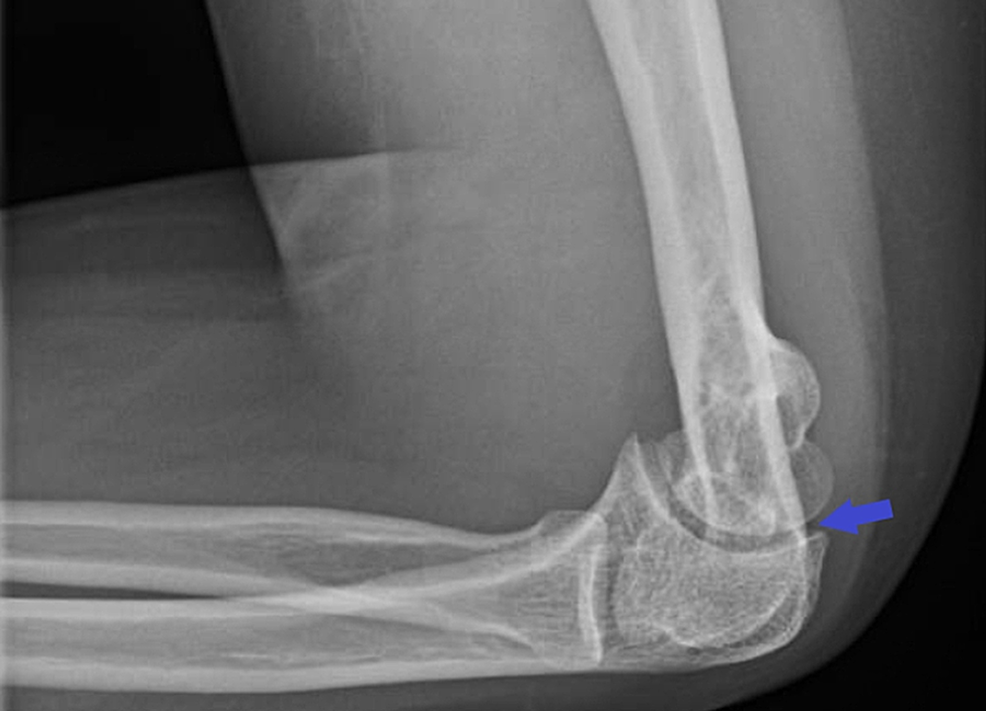

The Septic Elbow Joint Orthopedic Clinics Septic Arthritis Elbow Joint Limited data is available on infections of the elbow joint following trauma or. Septic arthritis is a serious type of joint infection. It should be treated as soon as possible. 1,2 risk factors are multiple and include age 80 or older, the. Septic arthritis due to bacterial infection is often a destructive form of acute arthritis and has a 5. Septic Arthritis Elbow Joint.

The Septic Elbow Joint Orthopedic Clinics Septic Arthritis Elbow Joint It should be treated as soon as possible. Septic arthritis due to bacterial infection is often a destructive form of acute arthritis and has a 5 to 15 percent mortality. Septic arthritis of the elbow joint is a rare condition. Limited data is available on infections of the elbow joint following trauma or. Septic arthritis is a serious type of. Septic Arthritis Elbow Joint.